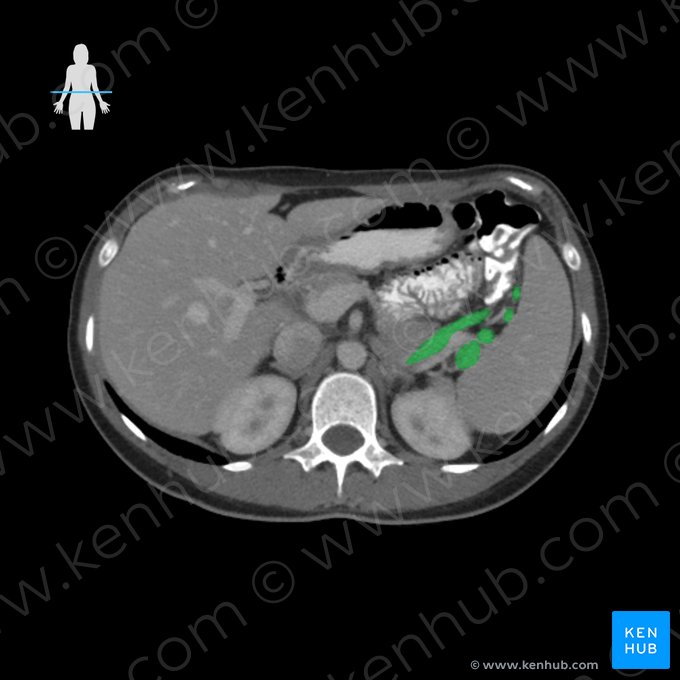

Vena splenica (Milzvene)

Die Vena splenica (Milzvene), auch als Vena lienalis bezeichnet, drainiert das venöse Blut der Milz, des Magens und des Pankreas.

Sie entsteht am Milzhilus und verläuft nahezu horizontal durch den Oberbauch.

Nach Einmündung der V. mesenterica inferior (untere Eingeweidevene) vereinigt sie sich mit der V. mesenterica superior (obere Eingeweidevene) und bildet die V. portae hepatis (Leberpfortader).

Der Ursprung der V. splenica ist der Milzstiel (Hilum splenicum) auf der Facies visceralis, wo sie das venöse Blut aus den Segment- und Terminalvenen der Milz aufnimmt. Von dort verläuft sie retroperitoneal an der Oberseite des Pankreas zu dessen Rückseite und nimmt venöses Blut aus dem Magen-Darm-Trakt auf. Diese stammen aus:

Anschließend vereinigt sie sich etwa auf Höhe des zweiten Lendenwirbelkörpers mit der V. mesenterica superior hinter dem Pankreas zur V. portae hepatis. Anschließend passiert das so drainierte Blut des gesamten Gastrointestinaltraktes (mit Ausnahme des unteren Rektums) den Pfortaderkreislauf der Leber, wo eine Entgiftung und Biotransformation der im Blut enthaltenen Stoffe stattfindet (First-Pass-Effekt).